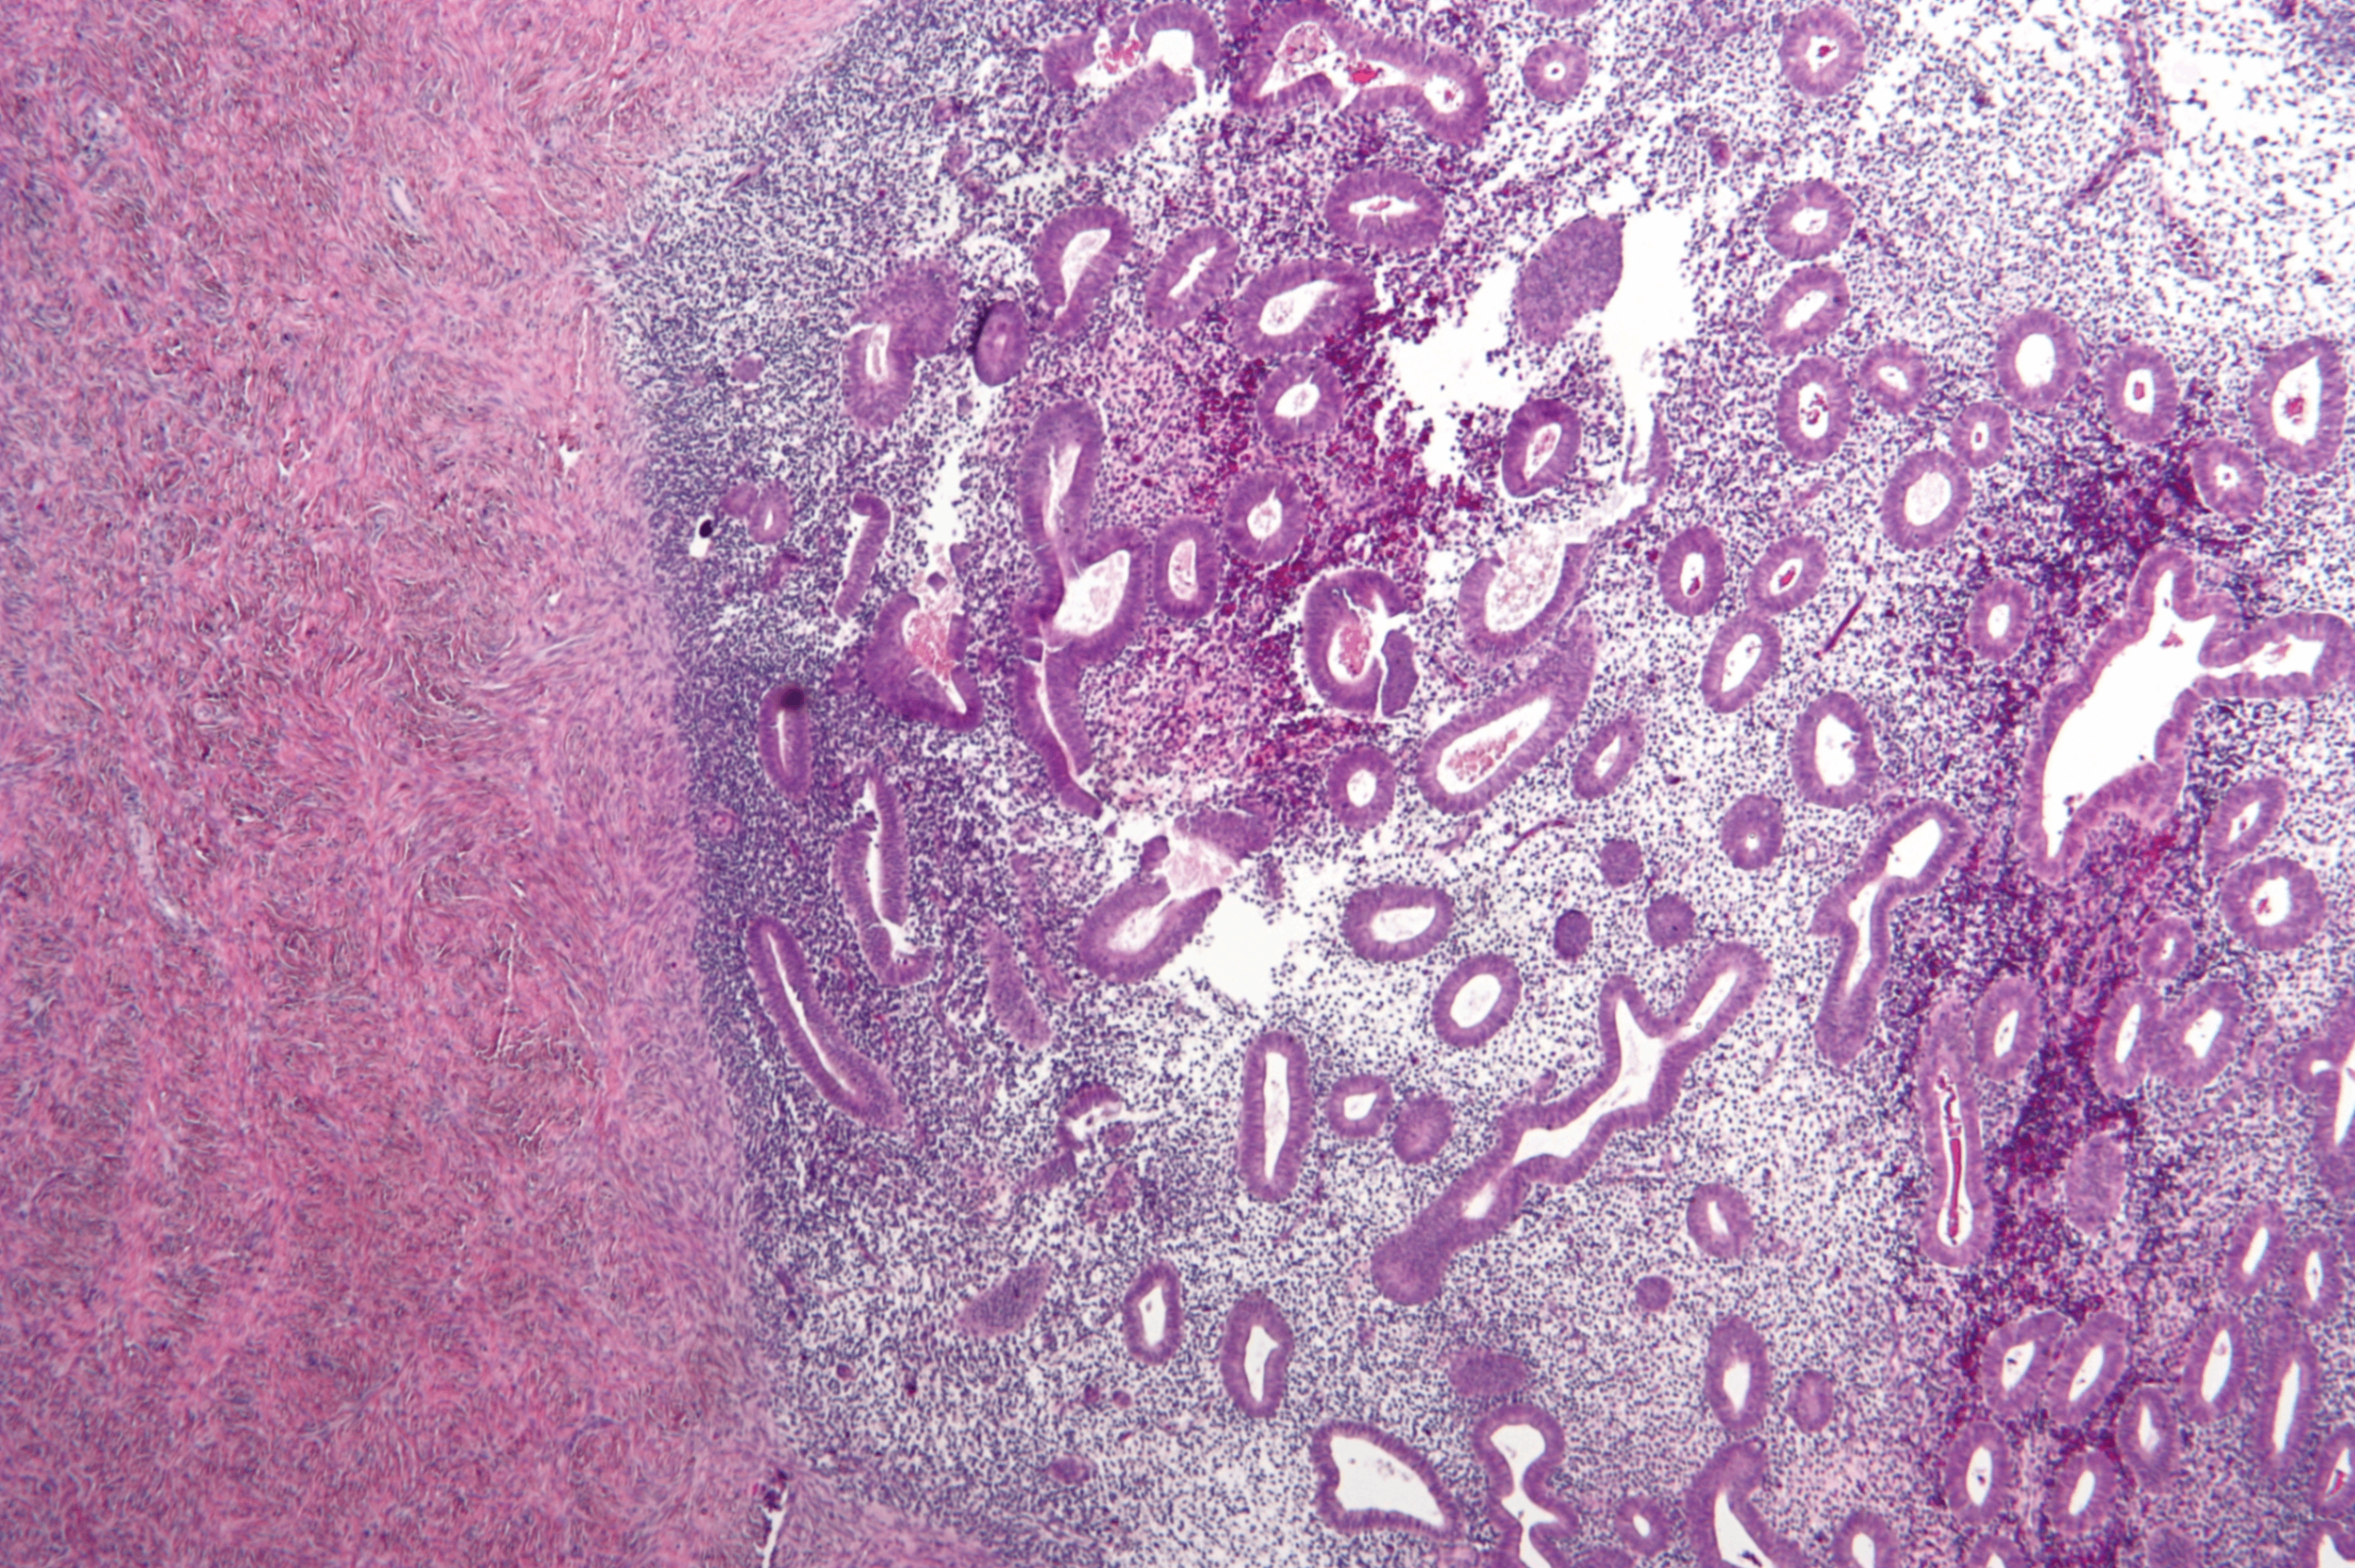

(1) 평활근종 (Leiomyoma)

자궁근종(fibroid)으로 불리며 가임기 여성에서 가장 흔한 양성 자궁 종양

평활근 세포 다발로 구성된 양성 종양; Atypia는 거의 없고 mitotic index 또한 낮다

• 초음파에서 잘 보이는 종괴로, 크기와 위치에 따라 증상이 다양함

• 대부분 무증상이나, 경우에 따라 과다출혈, 생리통, 방광 압박으로 인한 빈뇨, 불임, 유산 등을 유발

• 평활근육종으로의 진행은 흔치 않음

Leiomyoma, Wikipedia Commons